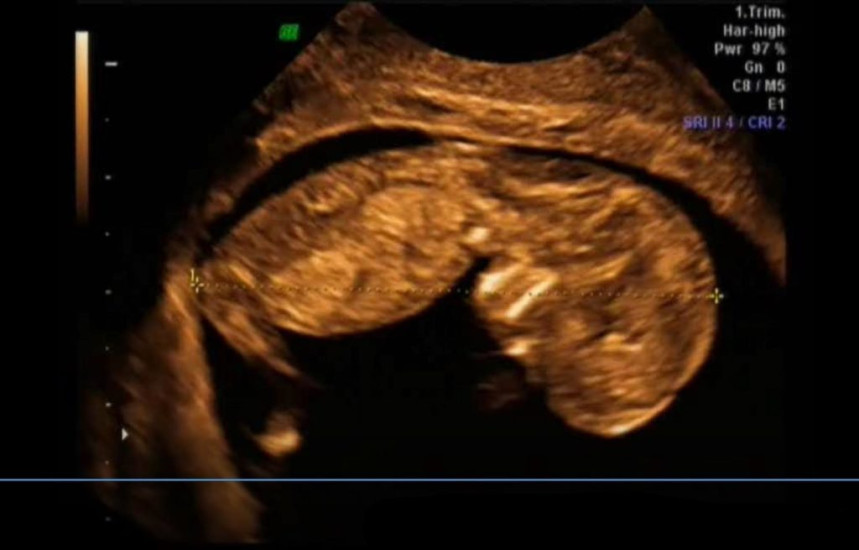

Maleństwo mierzy 7,5 cm długości i waży 14 g. Jest wielkości średniego jabłka.